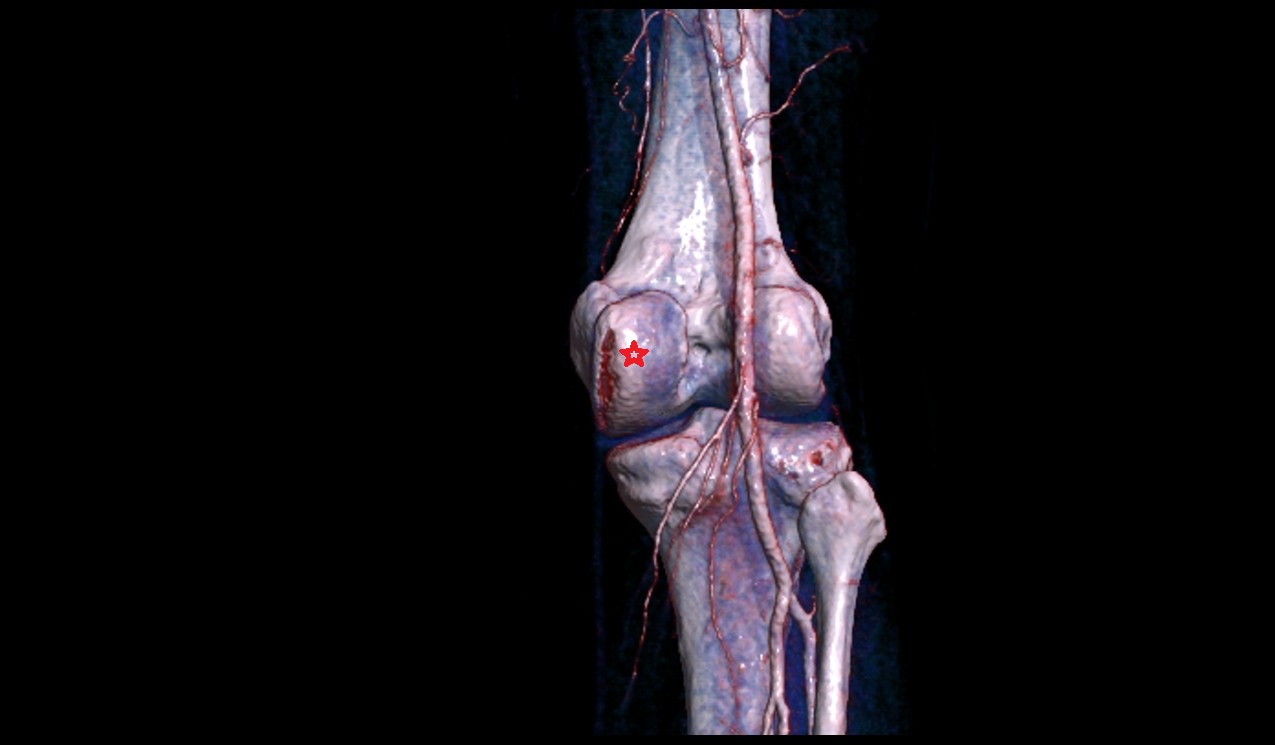

- Popliteal artery

- Superior medial genicular artery

- Superior lateral genicular artery

- Medial epicondyle of femur

- Lateral epicondyle of femur

- Lateral condyle of femur

- Medial condyle of femur